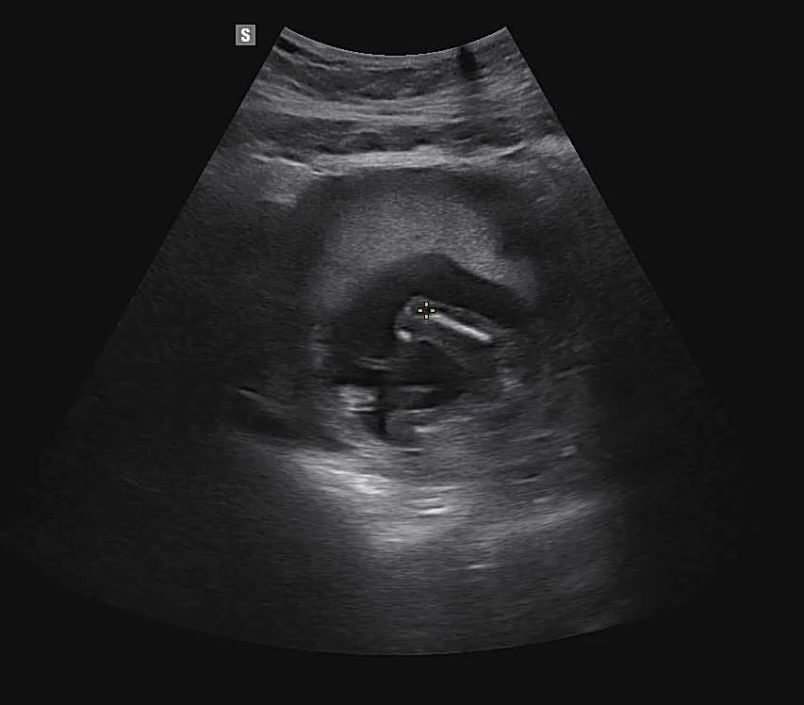

16주 아이 성별 공개 두둥!!

성별이 너무너무 궁금했지만 기다림끝에 의사선생님께 예쁜 공주님이라는 말씀 들으니 이제 더더욱 엄마가 되는구나를 느끼게 되는 요즘인 것 같아요!! 모두들 이제 다들 성별 확인하는 주차인데 저랑 같은 마음이실지 궁금해요~:)